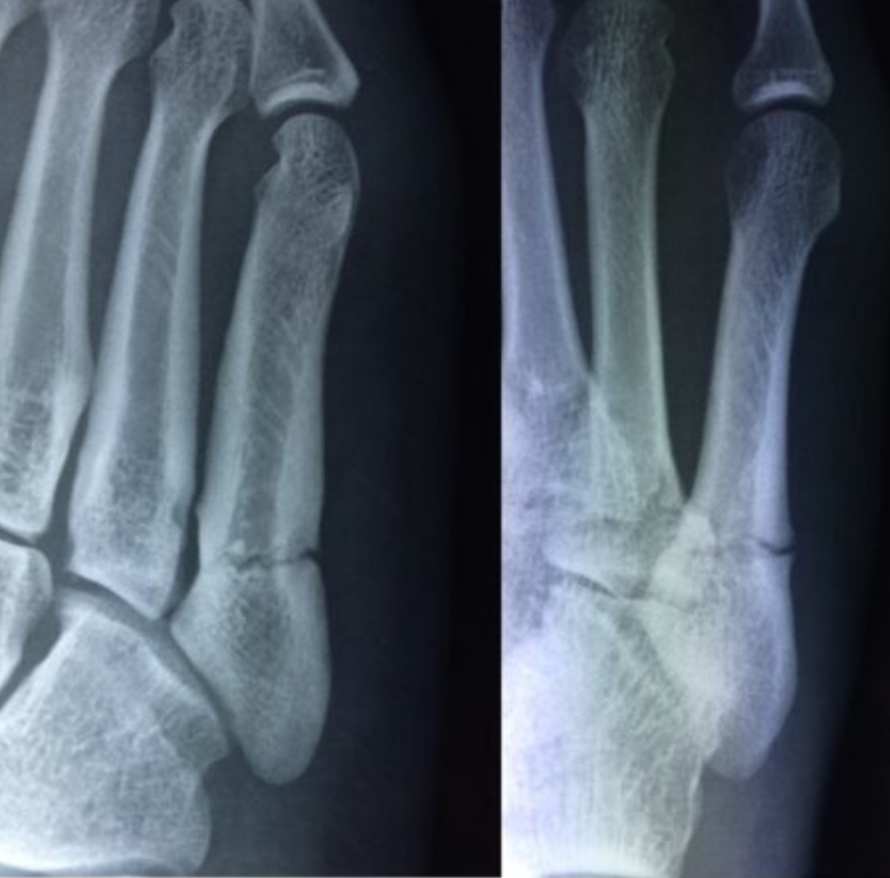

2020-12-09 スポーツ整形 ページ内リンク 第5中足骨骨折(ジョーンズ骨折)【スポーツ整形外科】 第5中足骨骨折(ジョーンズ骨折)【スポーツ整形外科】 サッカーやバスケット等の切り返しの多い競技にしばしば発生する。⇒スクリューによる固定で2〜3か月で復帰。 術前 術後 術後12週間 杉本 武 副院長/スポーツ整形外科センター長 整形外科スポーツ整形 詳しく見る 板野 佑生 整形外科スポーツ整形 詳しく見る 関連ページ スポーツ整形 一覧へ戻る